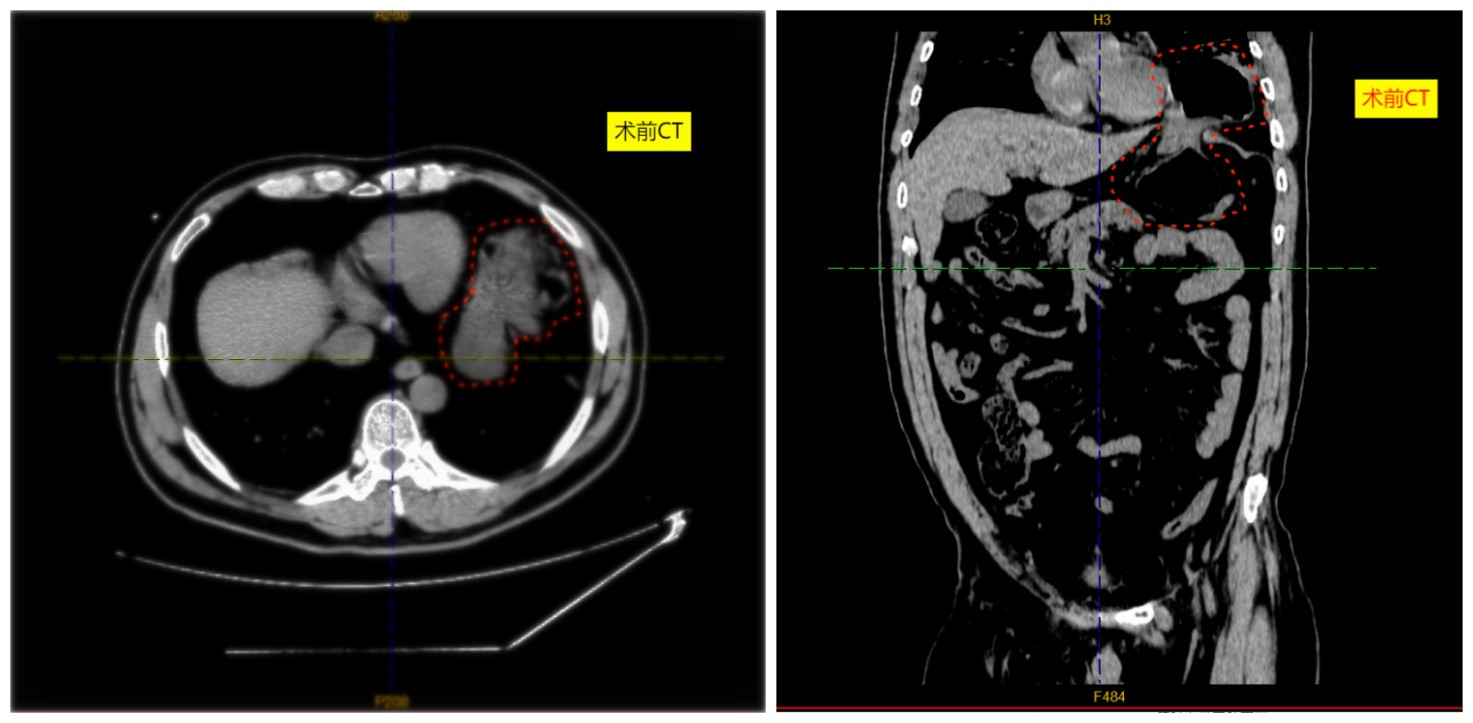

患者冯先生(化名),60岁,因“腹胀腹痛8小时”紧急来院。此前他曾有反复上腹痛史2年余,此次发病突然,疼痛剧烈。急诊CT检查提示:膈疝并嵌顿,由于疝内容物(约1/3胃及大网膜)已嵌入胸腔,如不及时处理,可能导致嵌顿组织缺血坏死、感染甚至危及生命,情况危急!

术前CT影像,显示胸腔内嵌顿脏器